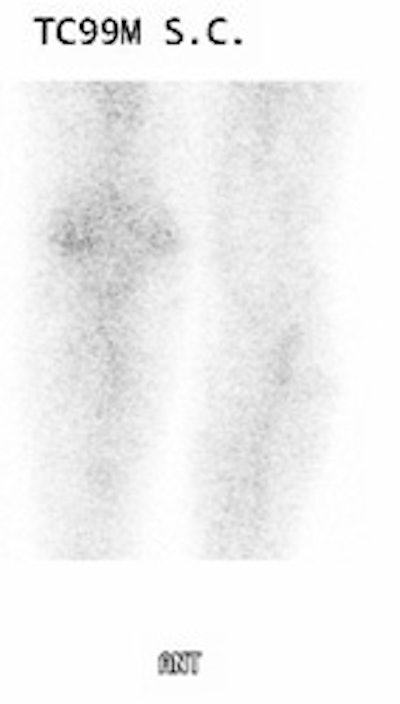

Presently, evaluation of a suspected infected joint prosthesis is best accomplished by combined In-111 WBC- Tc99m sulfur colloid scintigraphy [20]. Localized ectopic bone marrow expansion may occur in the appendicular skeleton after trauma (fracture), surgical interventions- such as joint prosthesis surgery, neuropathic joint, inflammation, or even calvarial hyperostosis [16,20]. Combined leukocyte-marrow imaging can overcome many of the problems created by variable marrow distribution post-operatively and should be used regularly. In leukocyte imaging it is neither the presence nor the intensity of labeled leukocyte activity, but rather the relationship of such uptake to bone marrow activity that is important [15]. Non-specific In-111 WBC accumulation within areas of ectopic bone marrow can be misinterpreted as infection [15]. The addition of Tc-sulfur colloid (Tc-SC) imaging can aid in evaluation of suspected prostetic hip infection by demonstrating normal bone marrow distribution. Any spatially incongruent area of In-111 WBC tracer activity which does not match marrow activity should be considered consistent with infection (regardless of the intensity of the tracer uptake) [15]. When the distributions of the two tracers are spatial congruent, the exam is negative for infection [15]. The intensity of WBC uptake can be misleading, even mild uptake is consistent with infection if it is spatially incongruent with marrow activity. Combined marrow scintigraphy using In-111 WBC's and Tc-sulfur colloid provides the best results for the evaluation of the suspected infected prosthesis with sensitivity, specificity, and accuracy greater than 90% [1,15,17,18,20].

Infected hip prosthesis: The patient shown below underwent evaluation for infected right hip prosthesis using combined In-111 WBC and Tc-sulfur colloid marrow imaging. The white blood cell exam demonstrated incongruent WBC accumulation along the mid and distal portions of the prosthesis (black arrows). Note that other areas of white blood cell accumulation are congruent with the bone marrow scan. The patient had an infected right hip prosthesis. |